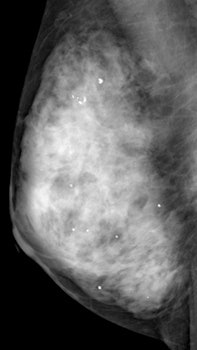

Adding ultrasound to mammography screening detects more early invasive breast cancer and probably reduces mortality, according to a 4 November study in the journal Lancet. The Japanese trial is thought to be the first of its kind in a large randomized multicenter population, and that focused on younger women at average risk with dense breast tissue.

Mammography is the only proven method of screening that reduces mortality, but it is inaccurate in dense breasts, Ohuchi and colleagues wrote. In Asia, where women characteristically have dense breast tissue, age-specific breast cancer incidence peaks in the younger age group of 40 to 49, compared with women 60 to 70 years old in Western countries.